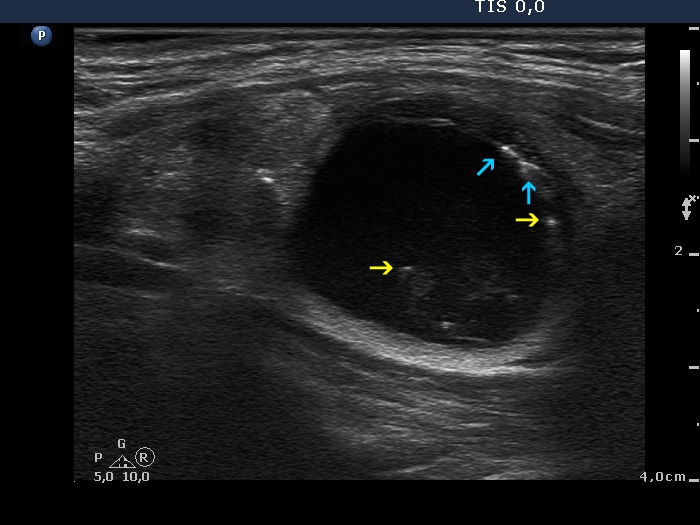

Benign cystic degeneration (cytological diagnosis) - case 662

|

It is worth analyzing the hyperechogenic figures in the central part of the cystic area. One in the horizontal view and another one in the longitudinal scan have a broader than usually fading tail. The figures pointed with arrows at the border of the cystic and solid part (right side of the nodule in the right image) are posterior back wall enhancement caused by the microcystic area ventral to them.